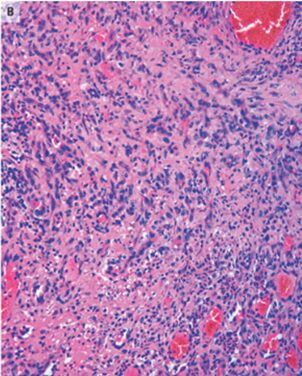

切除生検標本では増殖中の欠陥、線維芽細胞、多数の炎症細胞、および表面潰瘍形成が示され、化膿性肉芽腫と一致する所見が示された。

「化膿性肉芽腫」は唇、歯肉、指など頻繁な外傷部位に発生する可能性のある、急速に成長する良性の血管腫瘍。

名前に反してこれらの病変には膿も肉芽腫性病変も関与していない。